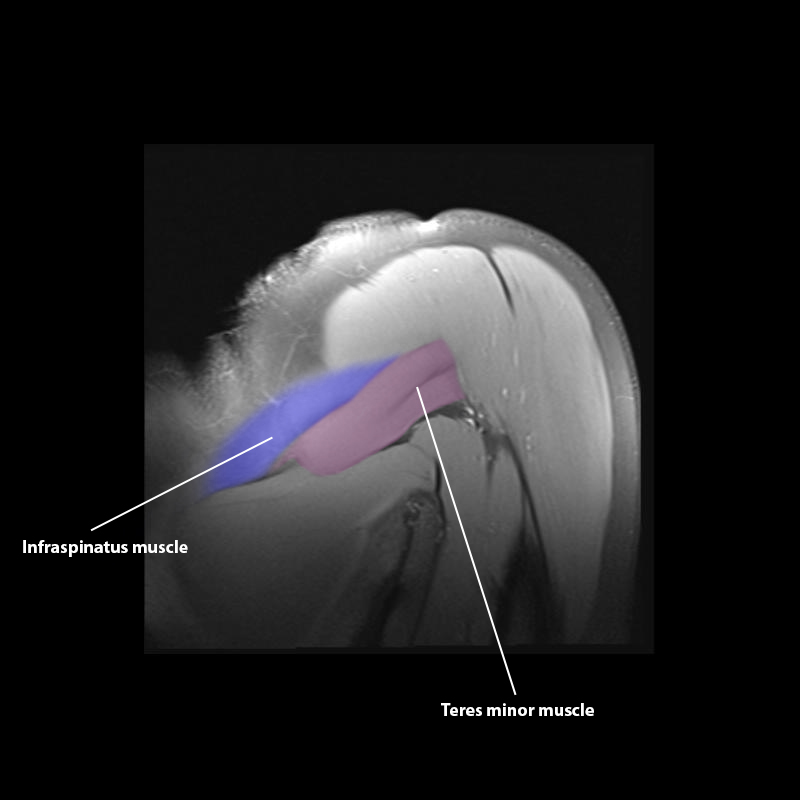

Shoulder MRI Anatomy